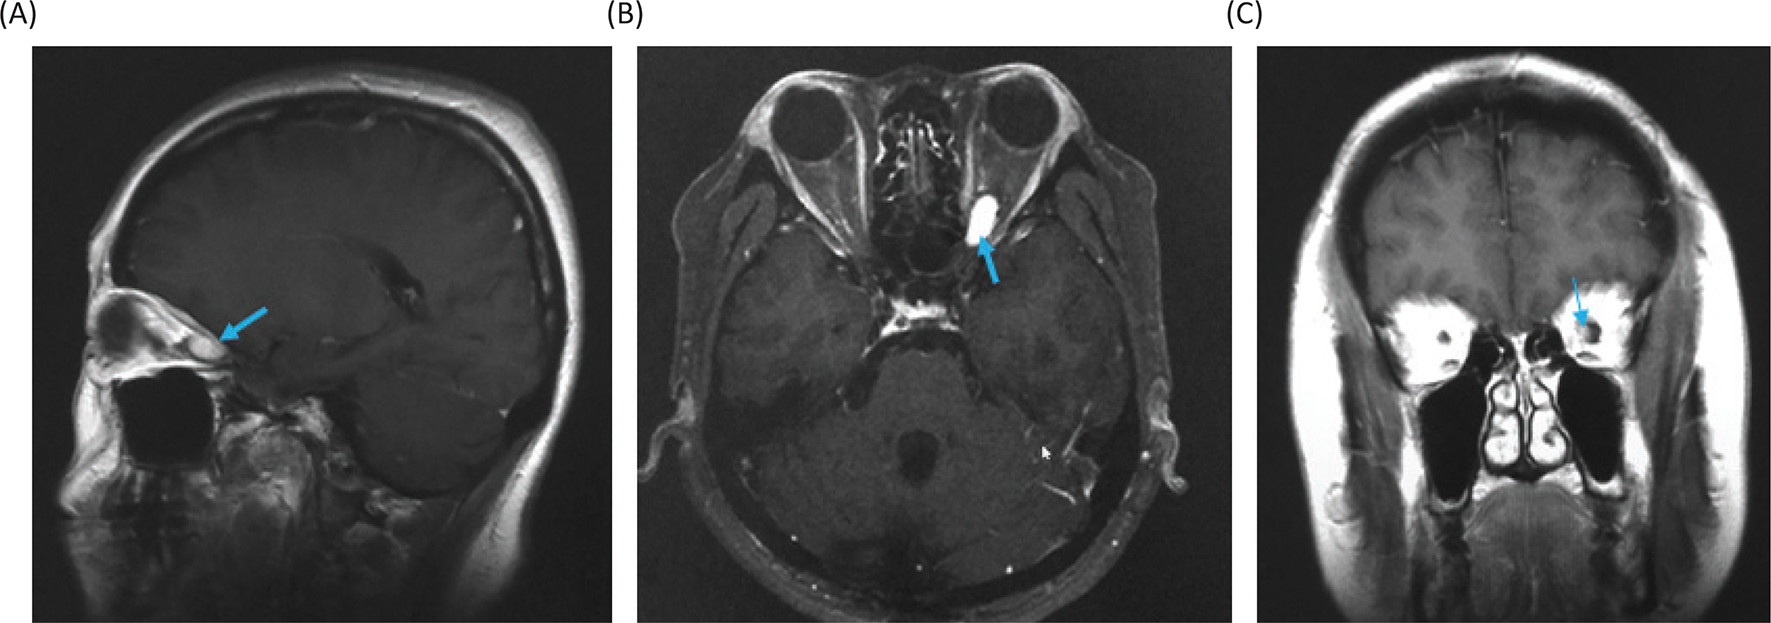

The differential diagnoses for the tumor include optic glioma, optic sheath meningioma, optic nerve schwannoma and optic nerve hemangioblastoma. Among them, since the patient is a VHL patient, the most probable diagnosis was thought to be an optic nerve hemangioblastoma. Therefore, we made a decision to treat the tumor with stereotactic radiosurgery. At Shonan Fujisawa Tokushukai Hospital, the stereotactic radiosurgery was prescribed with the dose being 39 Gy/13 fractions using Novalis. The planning target volume was set at 0.7 mL, and D95 (95% of standard irradiation volume) was set at 35 Gy/13 fractions. The patient completely lost her vision after the radiosurgery. Eighteen months after the radiosurgery, the tumor volume slightly decreased (Figure 5), but her vision has been still lost. The consent to publish the case has been given by the patient.

Fig 5

Figure 5. Gadolinium-enhanced magnetic resonance images at 18 months after the stereotactic radiosurgery. (A) Sagittal image. (B) Axial image. (C) Coronal image.